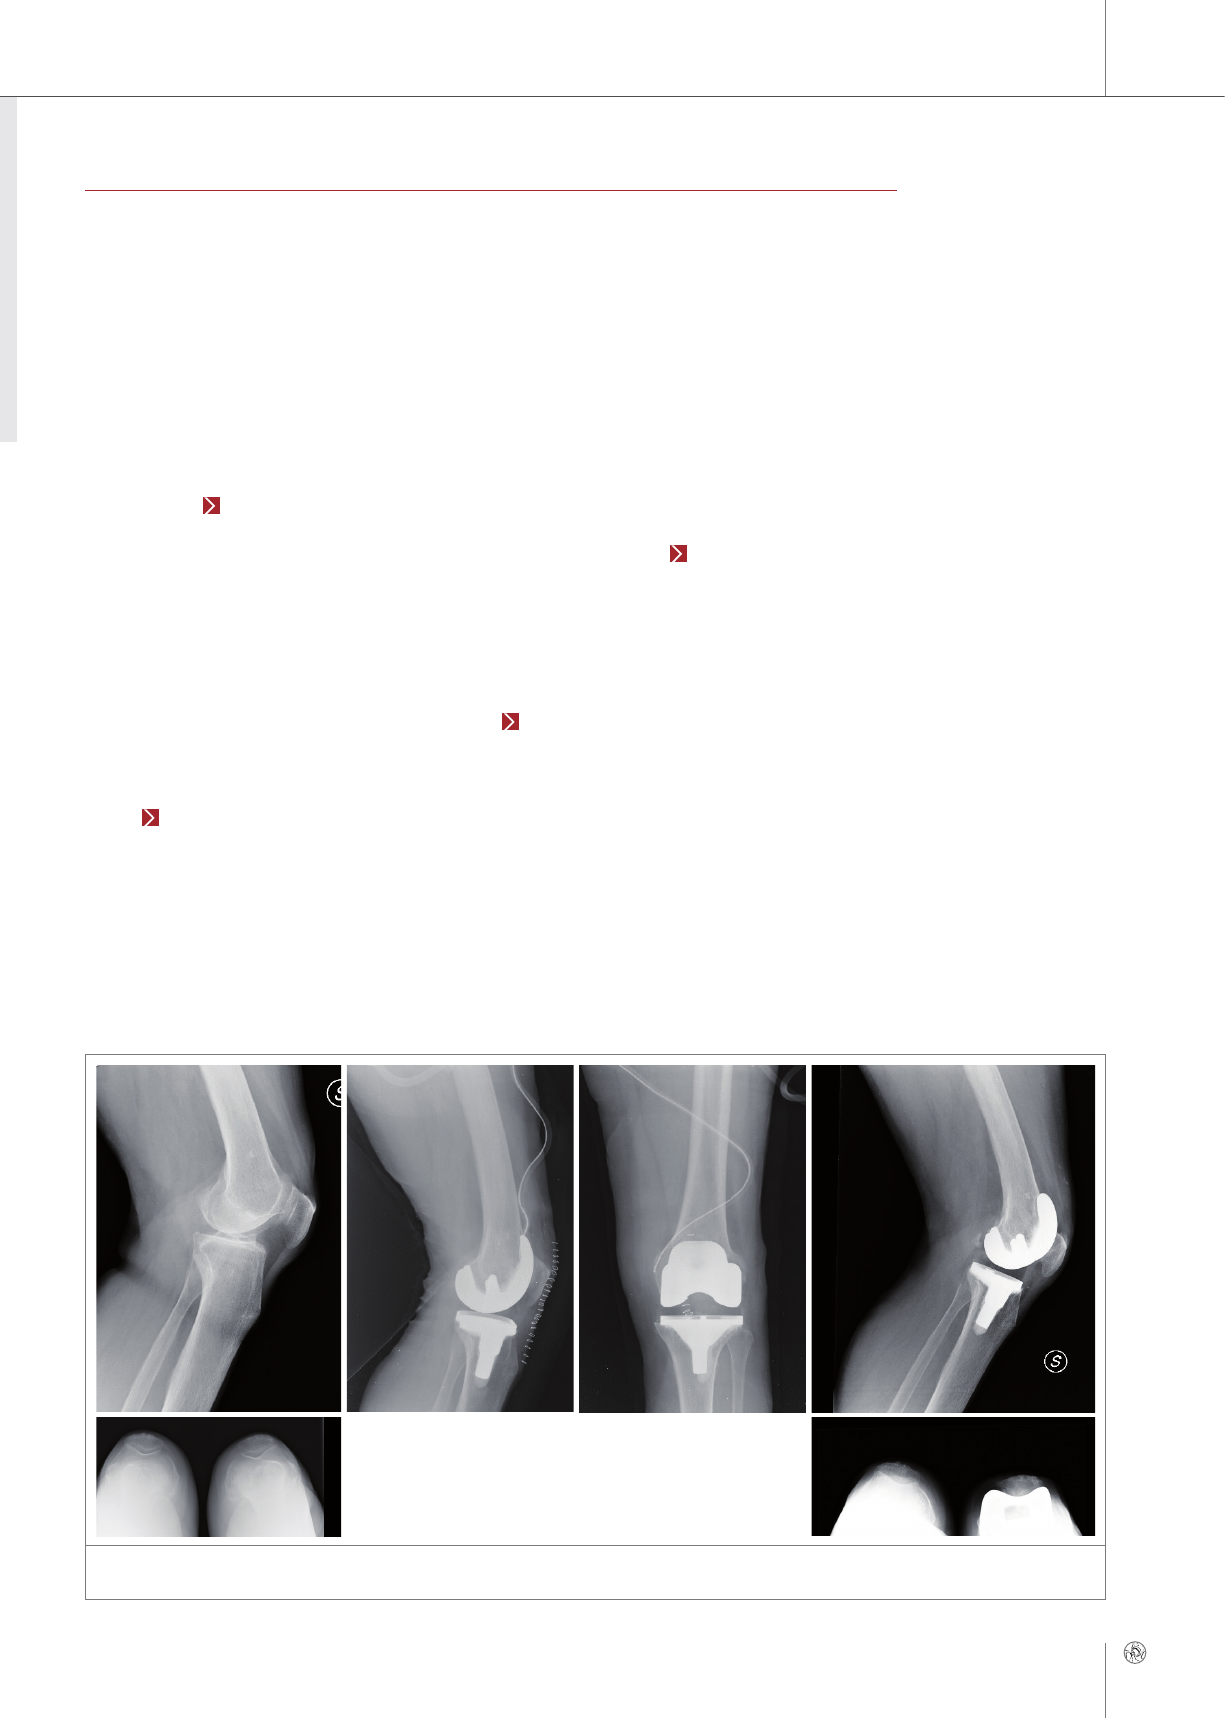

Primary TKR for advanced arthritis

Diagnosis

The patient was a 75-year-old woman with a history

of hypertension, pancreatic neuroendocrine cancer,

diabetes and glaucoma. She had had diffuse pain

in the left knee for 4 years which had been treated

without success with hyaluronic acid injections. The

X-rays showed a primary knee arthritis and a varus

knee. The cartilage degeneration involved all three

compartments (Fig. 2a), particularly the medial

side and the patellofemoral joint, and the mechani-

cal axis was medialized. She also had a metal allergy

(nickel), so we decided to use a the Multigen Plus

delta ceramic knee.

Therapy

Surgery was performed via a mini mid-vastus ap-

proach to the knee. Replacement of the knee was

performed with a fixed Ti tibial plate (size 1) and a

ceramic CR femoral component (Biolox®delta Mul-

tigen Plus, size 1) and a poly liner with a height of

12 mm (Fig. 2b).

Postoperative drug therapy consisted of peridural

analgesia, which allowed fast rehabilitation of the

knee: The patient began to exercise to restore the

range of motion on the first postoperative day, and

she walked with two canes on the second postop-

erative day. She took, as usual after a TKA, non-ste-

roidal anti-inflammatory drugs (indomethacin) for 3

weeks.

After 4 weeks she was able to do without one

cane and she had no pain. The range of motion was

0–110° and increased to 0–120° at 6 months.

The excellent results were confirmed at the last fol-

low-up at 2 years, and X-rays showed no radio-

lucent lines, a good patellar height and good pa-

tellofemoral tracking (Fig. 2c). The final clinical

KSS was 99 points (excellent), the final functional

KSS was 100 points (excellent), and the final OKS

was 46. ■

CASE REPORT 2

Figure 2: Knee of a 75-year old woman: a) preoperative status (lateral/patella), alle three compartments show arthritis damage, b) postoperative

with fixed tibial plate and ceramic femoral component (lateral/frontal), c) two years after surgical intervention (lateral/patella) (© Benazzo)